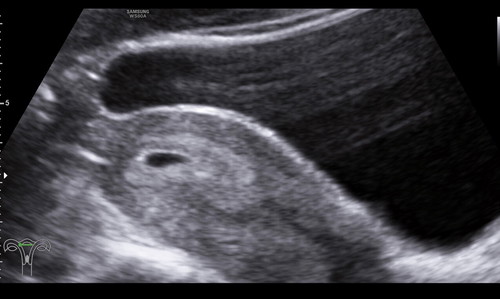

ไปหาหมอมาจ้าวันนี้ ปรากฎว่าการคำนวนระยะตั้งครรภ์ในแอฟกับผลซาวต่างกัน ในแอฟอายุครรภ์ 7+ แต่ผลซาว แค่ 5+ หมอบอกอาจจะเนื่องจาก ประจำเดือนมาไม่ปกติ ซาวมาเจอถุงตั้งครรภ์ในมดลูกปกติ แต่ยังไม่พบการเต้นของหัวใจ มีแม่ๆท่านไหนเคยเป็นแบบนี้มั้ยค่ะ

ยึดผลอัลตร้าซาวด์จากคุณหมอเป็นหลักค่ะ อายุครรภ์ยังไม่เยอะเลยเจอแค่ถุงการตั้งครรภ์ค่ะ ต่อไปก็จะเห็นตัวแล้วก็ได้ยินเสียงหัวใจค่ะ ค่อยๆเป็นค่อยๆไปทีละสเต็ปค่ะคุณแม่😊